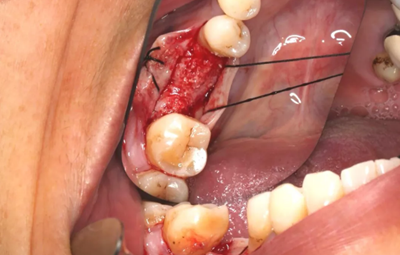

6、牙槽嵴保存術(shù)過程:拔牙及位點(diǎn)保存

(攝于2016年8月31日)

11、常規(guī)植入WEGO種植體一顆

牙槽嵴頂水平切口,翻瓣,牙槽嵴近中較遠(yuǎn)中豐滿。

(攝于2017年4月14日)